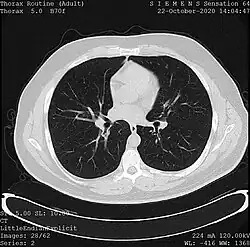

Tomography

Tomography is the imaging by sections or sectioning. The main such methods in medical imaging are:

- X-ray computed tomography (CT), or Computed Axial Tomography (CAT) scan, is a helical tomography technique (latest generation), which traditionally produces a 2D image of the structures in a thin section of the body. In CT, a beam of X-rays spins around an object being examined and is picked up by sensitive radiation detectors after having penetrated the object from multiple angles. A computer then analyses the information received from the scanner's detectors and constructs a detailed image of the object and its contents using the mathematical principles laid out in the Radon transform. It has a greater ionizing radiation dose burden than projection radiography; repeated scans must be limited to avoid health effects. CT is based on the same principles as X-ray projections but in this case, the patient is enclosed in a surrounding ring of detectors assigned with 500–1000 scintillation detectors[20] (fourth-generation X-ray CT scanner geometry). Previously in older generation scanners, the X-ray beam was paired by a translating source and detector. Computed tomography has almost completely replaced focal plane tomography in X-ray tomography imaging.